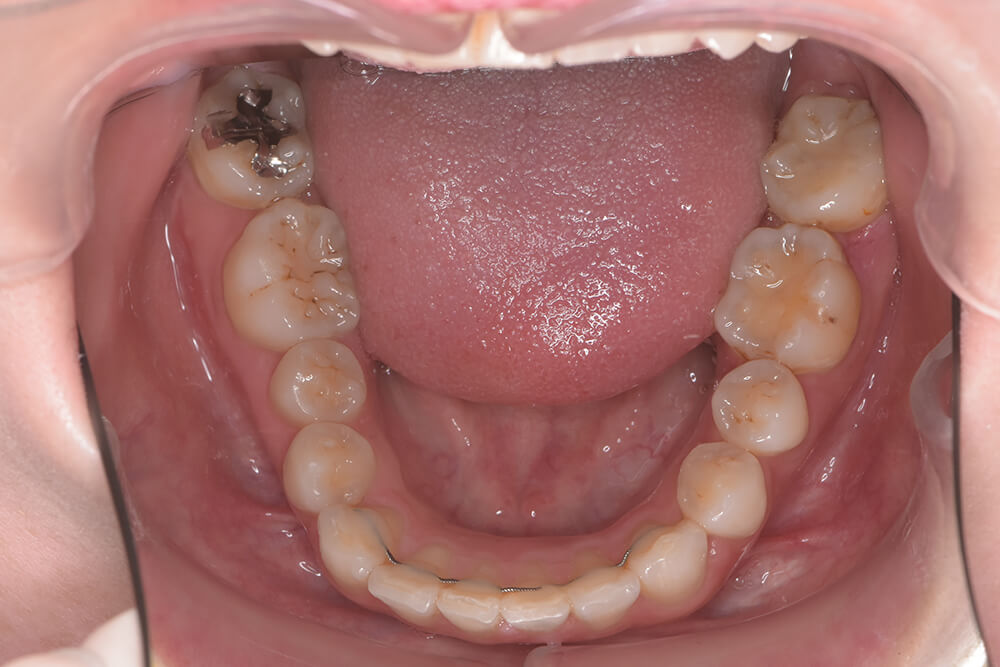

CASE03

After